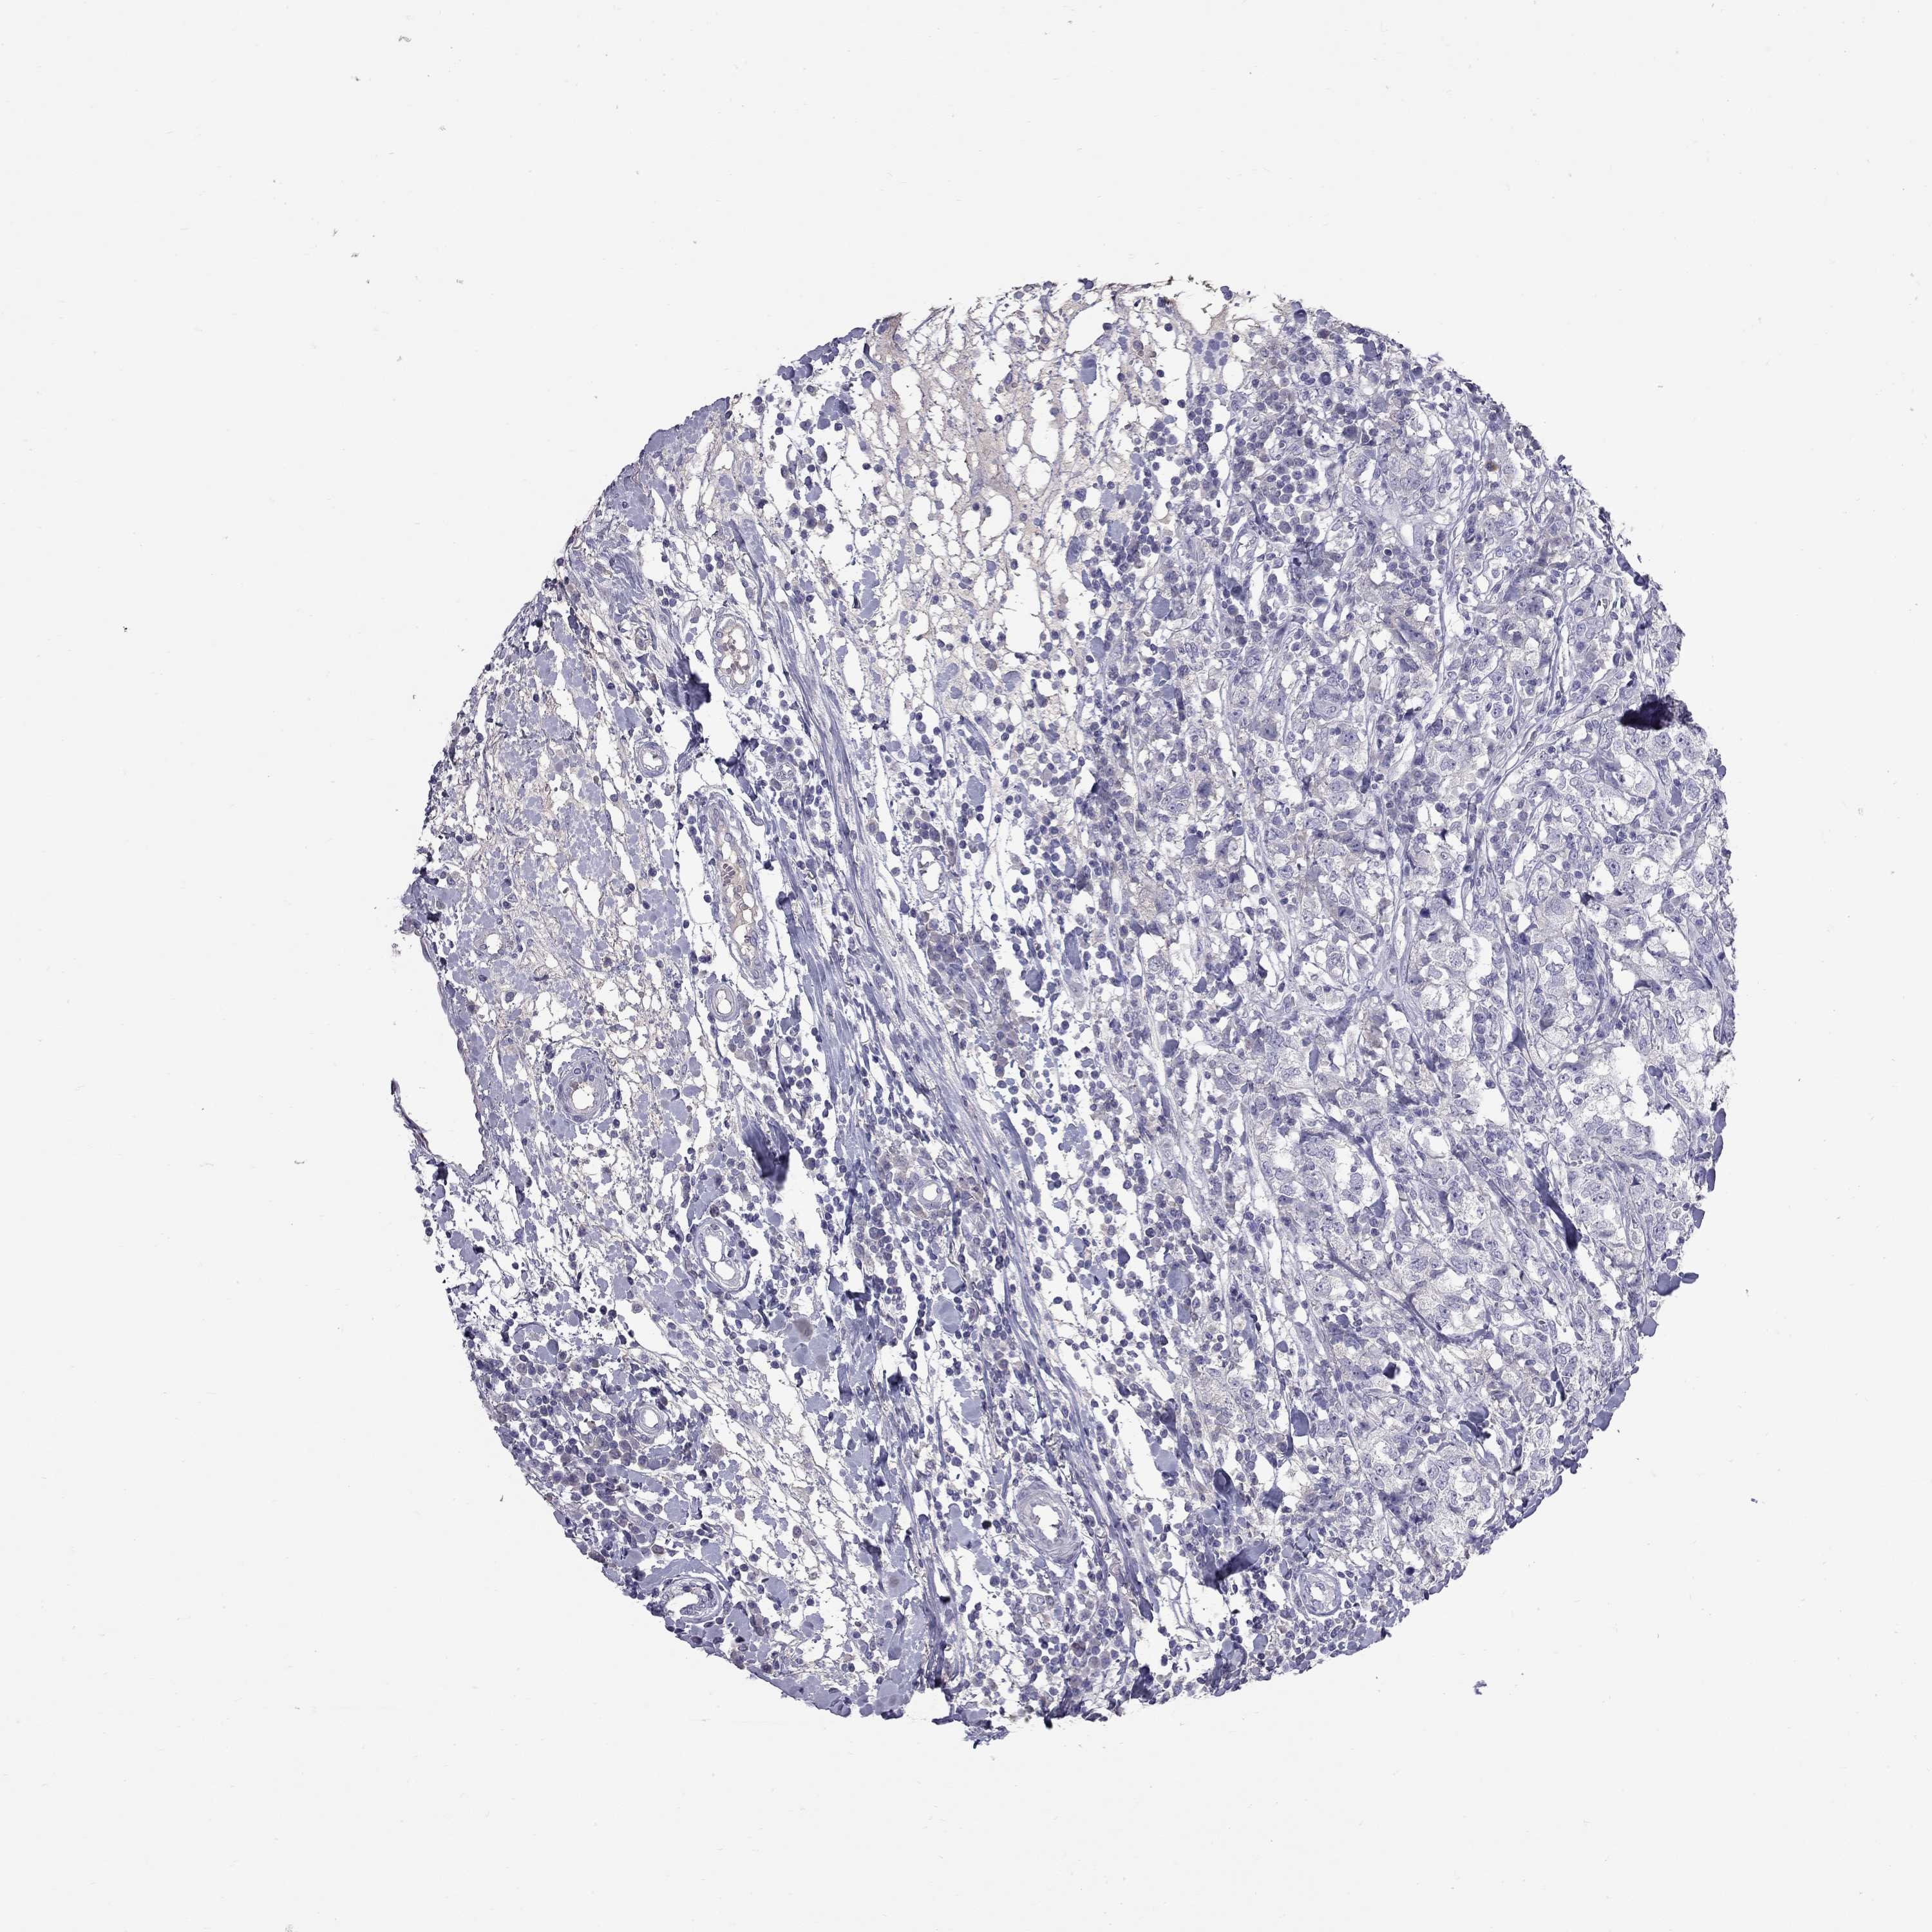

CANCER BREAST CANCER Show tissue menu

BRCA TCGA BRCA VALIDATION PROTEIN EXPRESSION